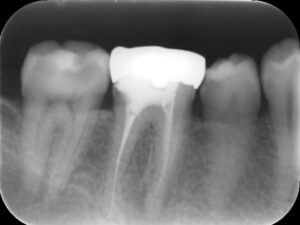

初診時レントゲン。右下の第一大臼歯に強い痛みを訴えて来院。すでに根管治療および補綴治療が行ってある。根管治療は行われているもの不十分であり、根尖部には黒いレントゲン透過像を認める。

根管充填時レントゲン。疼痛および頬部の腫脹が改善したため、根管充填を行った。根尖部まで緊密に根管充填されているのが分かる。